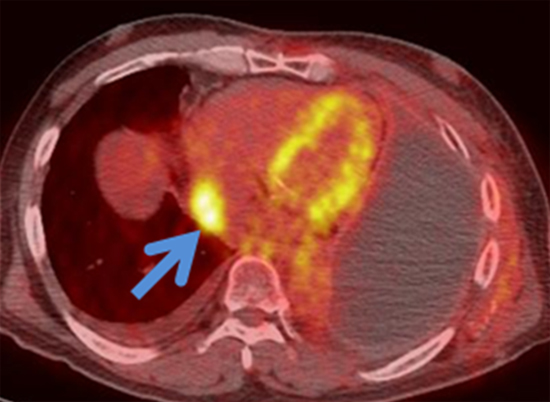

이 두 검사는 악성중피종의 흉곽 외 전이를 확인하는데 유용한 검사입니다. 특히 양전자방출단층촬영-전산화단층촬영 복합영상(PET-CT)이 전산화단층촬영(CT), 자기공명영상(MRI), 양전자방출단층촬영(PET)과 비교할 때, 2-3기 환자에서 수술이 가능한지를 결정하는데 더 정확하다는 것이 알려져 있습니다. 하지만, 이 두 검사 모두 종격동 림프절 전이 여부를 결정하는 데에는 위양성(실제는 전이 없는데 전이가 있다고 나오는 경우)과 위음성(실제는 전이가 있는데 전이가 없다고 나오는 경우)이 꽤 나오기 때문에 이 결과를 무조건 신뢰할 수는 없습니다.

[ 악성중피종의 양전자방출단층촬영-전산화단층촬영 복합영상: 좌측 폐에 대한 악성중피종의 수술적 치료 후 우측 심장부에 연하여 악성중피종이 재발한 소견입니다. 양전자방출단층촬영-전산화단층촬영 복합영상은 전이된 부위를 찾는데 유용합니다 ]